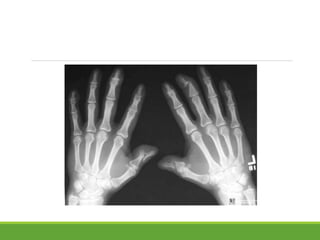

1.synovitis of diarthrodial joints

2.inflammation of fibro-osseous junctions and insertions of

tendons:enthesopathy

Synovitis of sacroiliac, vertebral facet joints, costovertebral joints or

peripheral joints:destruction of articular cartilage and periarticular

bone.